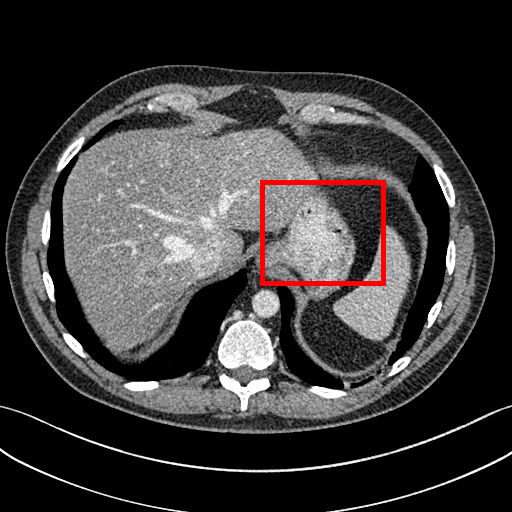

To demonstrate the effectiveness of the proposed network, we perform the qualitative comparisons over three representative abdominal images presented in Figs. 3, 5 and 7. For better evaluations of the image quality with different denoising models, zoomed regions-of-interest (ROIs) are marked by red rectangles and shown in Figs. 4, 6 and 8 respectively. Note that all results from different denoising models focus on two aspects: content restoration and noise-reduction. All CT images in axial view are displayed in the angiography window [-160, 240]HU.

The real NDCT images and corresponding LDCT images are presented in Figs. 3a and 3b. As observed, there are distinctions between ground truth (NDCT) images and LDCT images. Figs. 3a and 7a show the lesions/metastasis. Fig. 5a presents focal fatty sparing/focal fat. In Figs. 4a, 6a and 8a, these lesions can be clearly observed in NDCT images; in contrast, from Figs. 4b, 6b, and 8b, it can be seen that the original LDCT image is noisy, and lacks structural features for task-based clinical diagnosis. All adopted denoising models suppress noise to some extent.

To evaluate the effectiveness of our proposed objective function, we compare our method with existing WGAN-based networks, including WGAN and WGAN-VGG. Considering the importance of clinical image quality and specific structural features for medical diagnosis, we adopted the adversarial learning method [41, 42] in our experiments because WGAN could help to capture more structural information. Nevertheless, based on our prior experience, utilizing WGAN alone may yield stronger noise than other selected approaches, because it only maps the data distribution from LDCT to NDCT without consideration of local voxel intensity and structural correlations. The observations demonstrate that the noise texture is coarse in the images, as shown in Fig. 4g and Fig. 8g, which support our intuition.

Indeed, the images of WGAN-VGG[37], as shown in Fig. 3j, exhibit better visual quality with respect to more details and share structural details similar to NDCT images according to human perceptual evaluations. However, Figs. 4j (marked by the red circle) and 6j (marked by the green circle) suggest that it may severely distort the original structural information. A possible reason is that the VGG network [47] is a pre-trained deep CNN network based on natural images, and the structural information and contents of natural images are different from medical images.

Compared with WGAN and WGAN-VGG, our proposed SMGAN-3D, as shown in Figs. 4l (marked by the red circle) and 6l (marked by the green circle), can more clearly visualize the metastasis and better preserve of the portal vein.